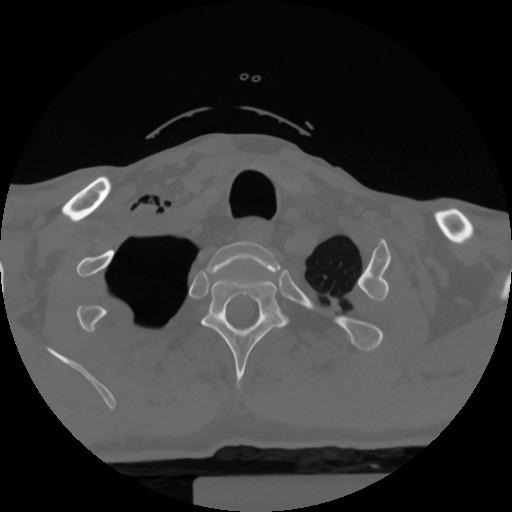

12 P.BLANDAS,,Vol,0.5,P.BLANDAS,,